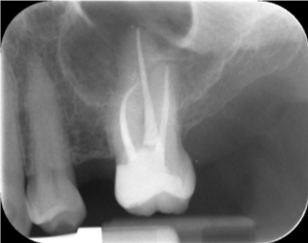

Tijdens de behandeling worden er enkele röntgenfoto’s genomen om het verloop van de behandeling te controleren. Vaak zal deze behandeling in twee zittijden gebeurden doordat dit een intensieve en lange behandeling is.